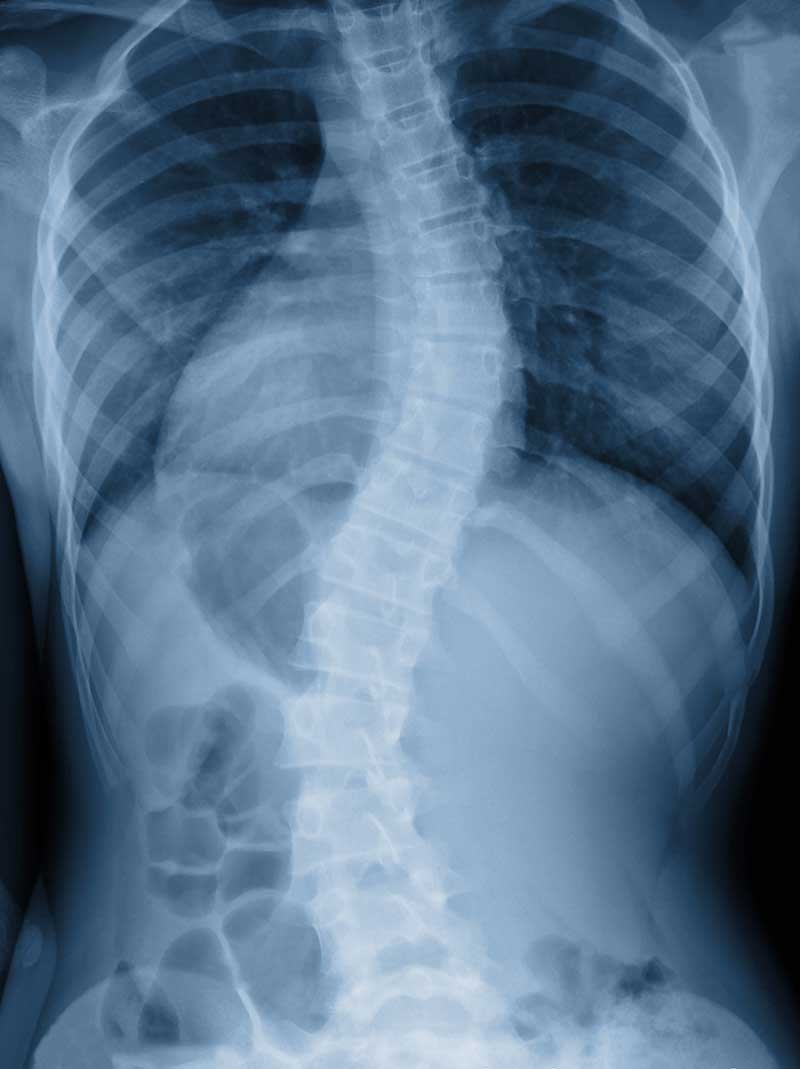

Scoliosis causes the spine to curve in an S or C shape, which forces surrounding muscles to compensate unevenly over time. This leads to one-sided fatigue, tightness, and discomfort that tends to worsen with prolonged standing, sitting, or carrying. Dr. Sitzmann takes time to understand how your specific curve interacts with your work, lifestyle, and daily habits before building a care plan.